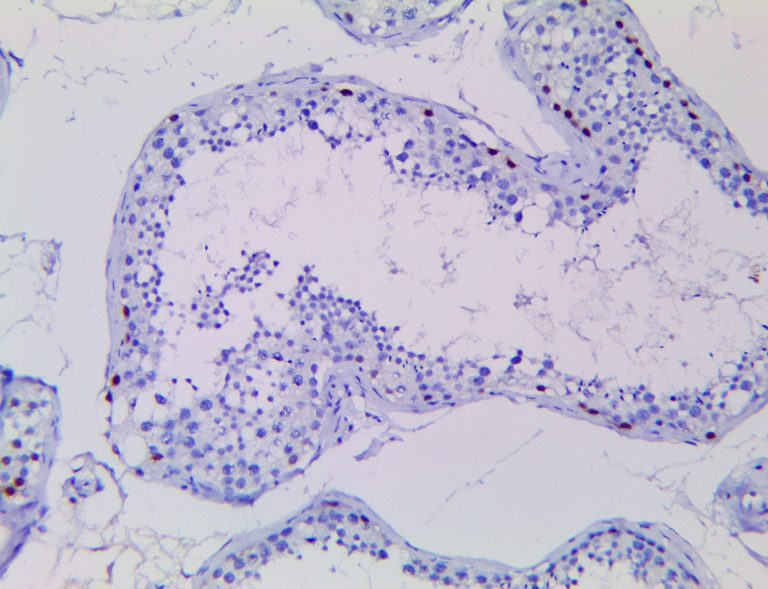

It is the ICU physician who is most likely to witness one of the deadliest manifestations of the abnormal immunological response, the cytokine storm syndrome (CSS). This response is also referred to by some as the cytokine release syndrome (CRS). CSS is characterized by continuous activation and expansion of macrophage and lymphocyte populations, which secrete large amounts of cytokines, causing the cytokine storm. This massive cytokine release is akin to hemophagocytic lymphohistiocytosis (HLH) disease, a syndrome characterized by initial unchecked and persistent activation of cytotoxic T lymphocytes and NK cells.

Clinical and laboratory manifestations of HLH include fever, enlarged liver and/or spleen, neurologic dysfunction, coagulopathy, liver dysfunction, cytopenias (i.e., low levels of erythrocytes, leukocytes, and/or platelets), hypertriglyceridemia, hyperferritinemia, hemophagocytosis, and eventually diminished NK cell activity as the immune system becomes progressively paralyzed. HLH can be familial (primary HLH) or secondary to another disease process (sHLH), such as rheumatic disease, in which it is referred to as macrophage activation syndrome (MAS, characterized by elevated ferritin).